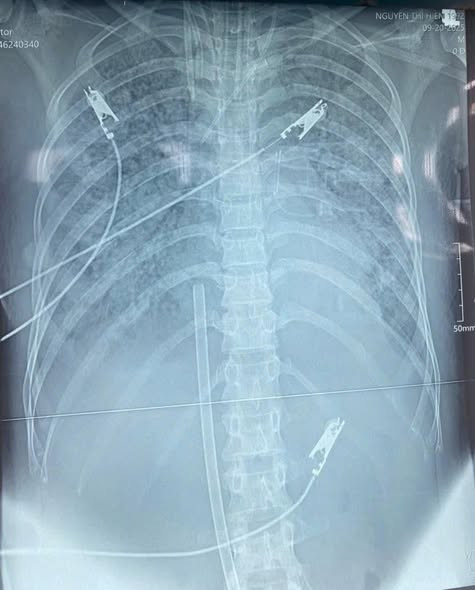

Các bác sĩ áp dụng kỹ thuật Hybrid ECMO (V-A-V ECMO) hồi sinh sự sống cho bệnh nhân/ Ảnh Bệnh viện Hữu nghị Đa khoa Nghệ An

Các bác sĩ khoa Hồi sức tích cực đã quyết định triển khai kỹ thuật tim phổi nhân tạo ECMO, giải pháp được coi là “cứu cánh cuối cùng” trong hồi sức. Điểm đặc biệt của ca bệnh là bệnh nhân vừa huyết áp thấp dù đã sử dụng ba vận mạch, trợ tim phối hợp liều cao vừa suy hô hấp rất nặng, do đó một chế độ ECMO đơn thuần không thể đáp ứng. Các bác sĩ đã lựa chọn Hybrid ECMO (V-A-V ECMO) – sự kết hợp đồng thời giữa VV-ECMO và VA-ECMO, vừa hỗ trợ hô hấp, vừa hỗ trợ tuần hoàn.

Kỹ thuật Hybrid ECMO vừa hỗ trợ hô hấp vừa hỗ trợ tuần hoàn giúp cứu sống bệnh nhân sốc nhiễm khuẩn, viêm phổi biến chứng ARDS mức độ rất nặng, tổn thương cơ tim cấp, suy đa tạng.